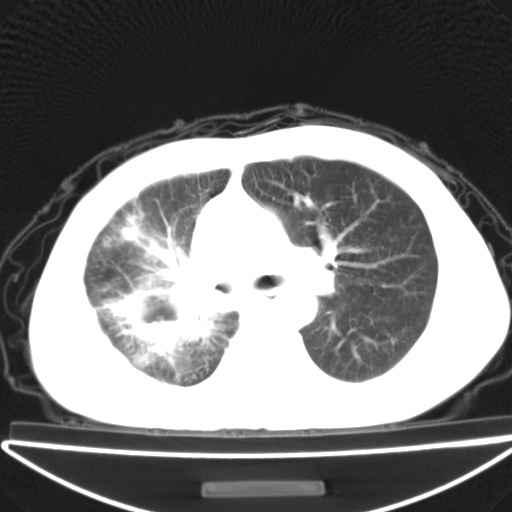

以下是引用jsgdoctor在2008-11-6 22:12:00的发言:[br]右主支气管壁明显增厚,管腔狭窄.考虑为右侧中央型肺癌伴阻塞性炎症\\肺脓肿.

以下是引用zjzjr在2008-11-6 20:25:00的发言:[br]中心型肺ca,合并阻塞性肺炎

以下是引用zsl6918在2008-11-6 19:43:00的发言:[br]右侧中心性肺癌(鳞癌)